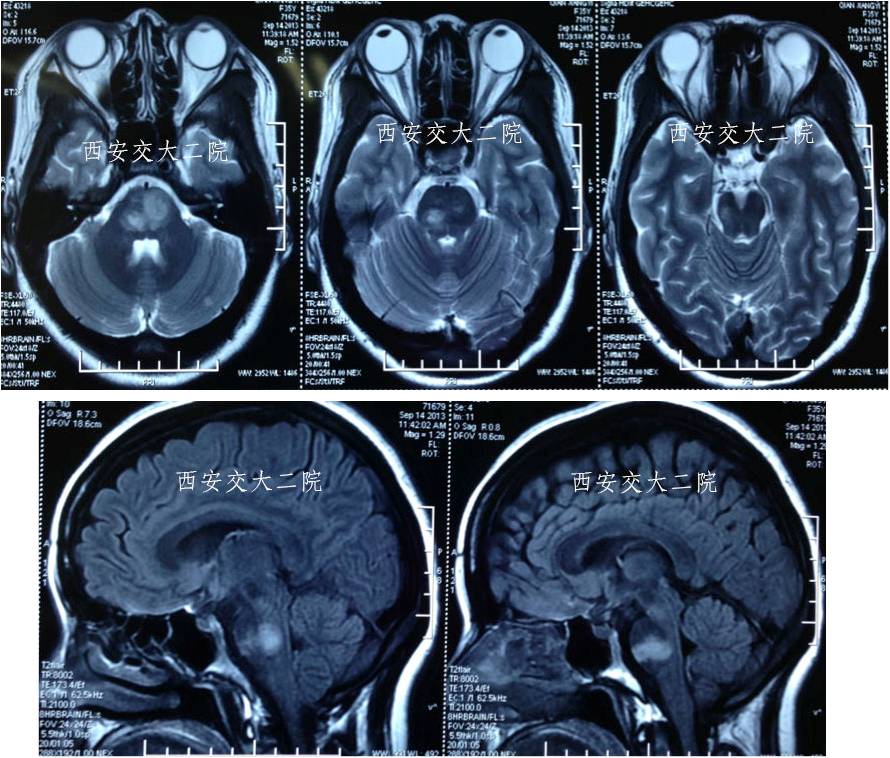

术后10天MR

术后10天MRA